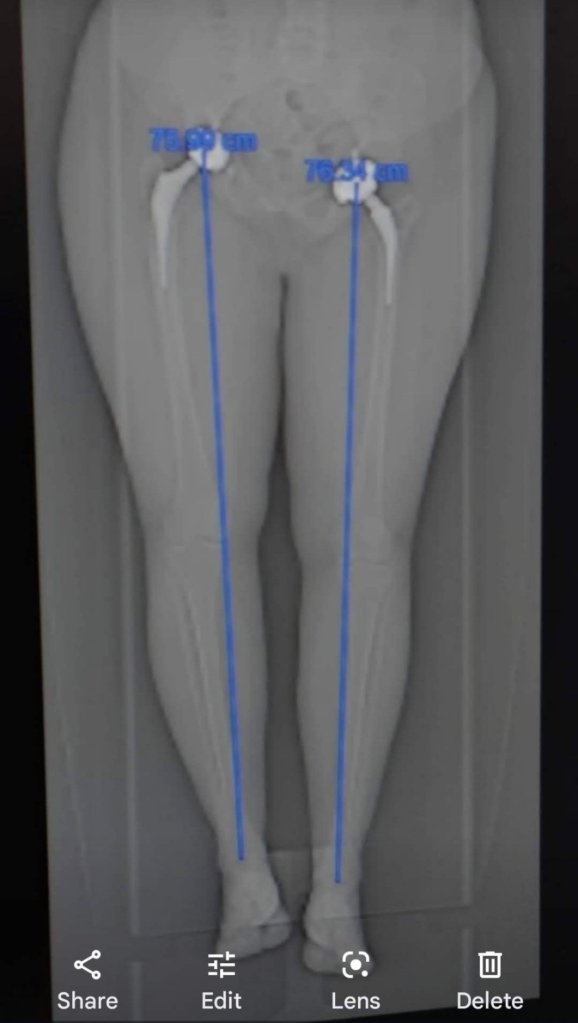

After a horrific journey that was stressful, we arrived, sweaty and overwhelmed. The doctor is calming in nature and softly spoken, so we listen intently. It’s Scoliosis there are 2 slight curves in the spine. At the Cervical and Thorasic areas (neck and chest) and as the hips are now technically measuring correctly, it’s highlighted this spinal curve.

Now I need referring to a spinal specialist, and need to ask him if insoles will make it worse, as this doctor thinks it could. She was saying perhaps all along the spine had referred pain to the hips (I disagree) and when I fixed them it flared this up, but I’ve had 10 hip surgeries, and this only started after my 10th one! Never before have I had such an intense back pain all day every day like I do now.